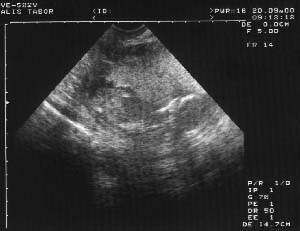

V pondělí jsem byla na kontrole. Přibrala jsem zatím asi 4 kg, tlak mám v normě, cukr a bílkoviny v moči žádné. Bříško už se mi trošku zvedá, ale zatím to není ještě moc poznat, nosím normální oblečení, ne těhotenské. Paní doktorka mi řekla, že jsem v pořádku a že mě pokud možno chce vidět ještě tento týden na ultrazvuku. A tam nás čekalo další překvapení. Dvojčata se nekonají, miminko bude jen jedno. Samozřejmě, že tam druhé může být, ale prý to není pravděpodobné.